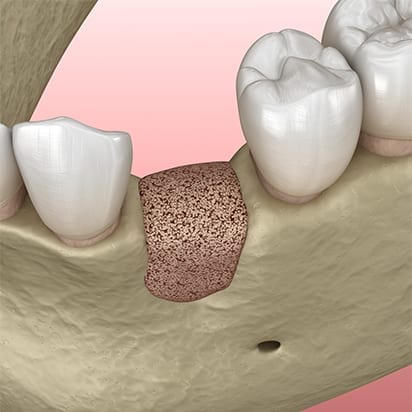

Depending on your particular case we will use either particle graft material, or block grafts, or both. Particle graft material is packed into and around an area with insufficient bone, whereas block grafts are screwed into the jawbone.

Particle graft material: